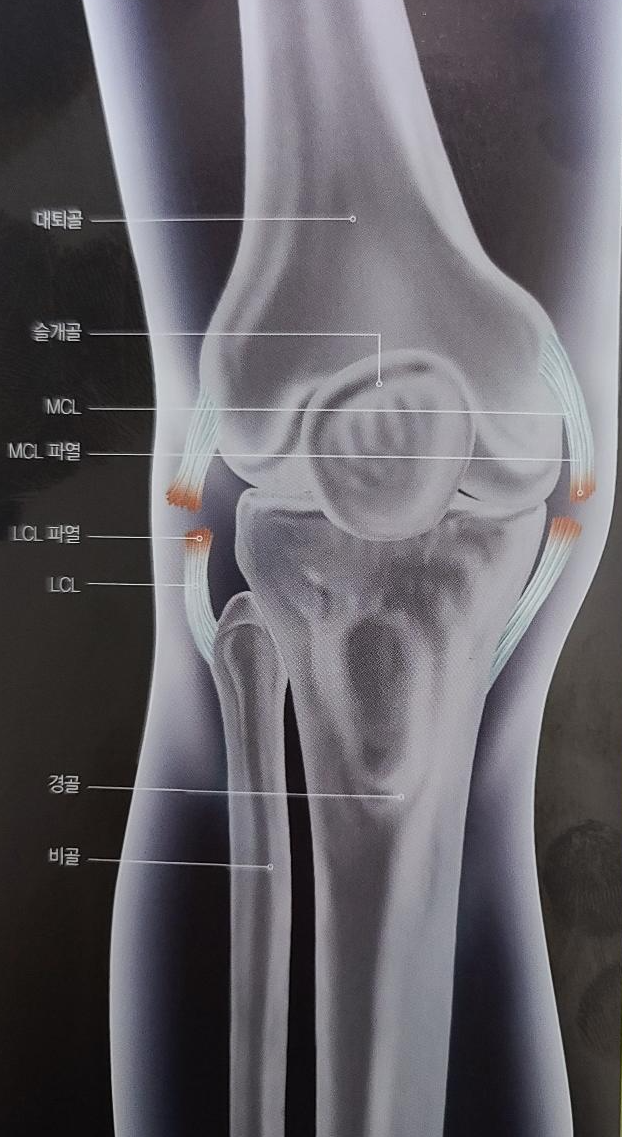

내측 측부인대는 럭비, 축구와 같은 충돌형 스포츠에서 많이 손상이 되는 부위입니다.

내측 측부인대의 역할은 무릎이 안쪽으로 붕괴되는 것을 막아주는 역할을 합니다.

1. 내측 측부인대 손상의 원인?

무릎 바깥쪽에 직접적인 타격을 받으면 내측 측부인대 파열이 발생합니다.

이 부상은 럭비, 축구 또는 육상선수가 달리거나 점프를 할 때 무릎이 비정상적인

스트레스가 가해지면 유발됩니다. 이와 관련하여 무릎 인대 염좌, 파열도 흔히 일어납니다.